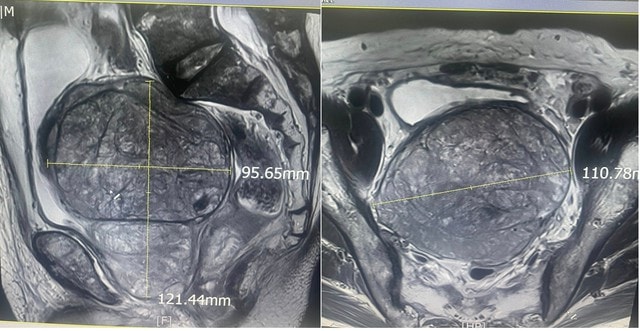

Các bác sĩ Khoa Ngoại – Tiết niệu, Bệnh viện Hữu Nghị vừa phẫu thuật thành công cho bệnh nhân nam 83 tuổi có tuyến tiền liệt kích thước "khủng" lên tới 600 gram – gấp hàng chục lần so với bình thường.

Trước phẫu thuật, bệnh nhân nhập viện trong tình trạng tiểu khó kéo dài, bí tiểu tái diễn nhiều lần, kèm theo rối loạn tiêu hoá do khối u tuyến tiền liệt khổng lồ chèn ép trực tràng.